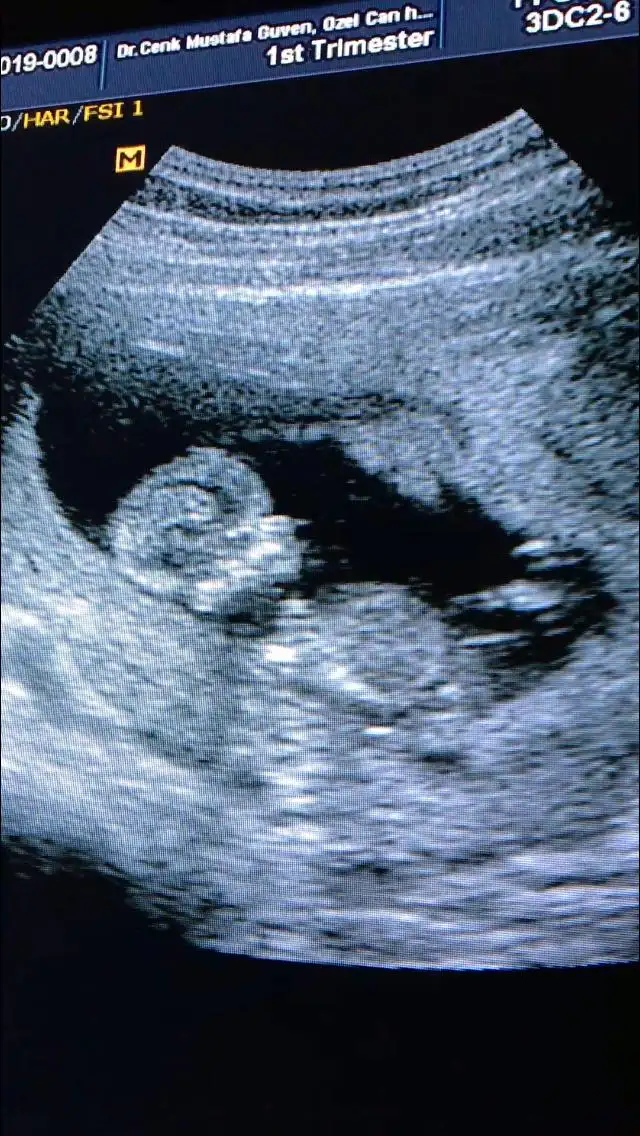

İkili için ölçümlerim güzel çıktı. Ense 1,25 çıktı. Çok iyi dedi doktorum. 3 ün üstü riskmiş. Burun kemiği var. Başka bişiler daha dedi hatırlamıyorum. Baş popo mesafesi günüyle uyumlu. Kan sonuçları 10 gün sonra çıkcak. Bizim kuzu uyuyordu rahat rahat ölçtü biçti doktor. Ama sonra dürttü göbeğimi ultrason cihazıyla. Zıplamaya başladı. Rahatsız oldu tipsiz :)

Cinsiyet sorduk. Kesin olmamakla beraber kız diyelim dedi ama o esas 16 da belli olur dedi. Zaten tam göremiyorlarsa genelde kız oluyor. Erkek tam gösteriyor o sebeple ben kız olarak bekliyorum valla :)

Videoya da çektim.

Bu da benim kızçem. Nub ( çıkıntı) bakmak isteyenler için :)